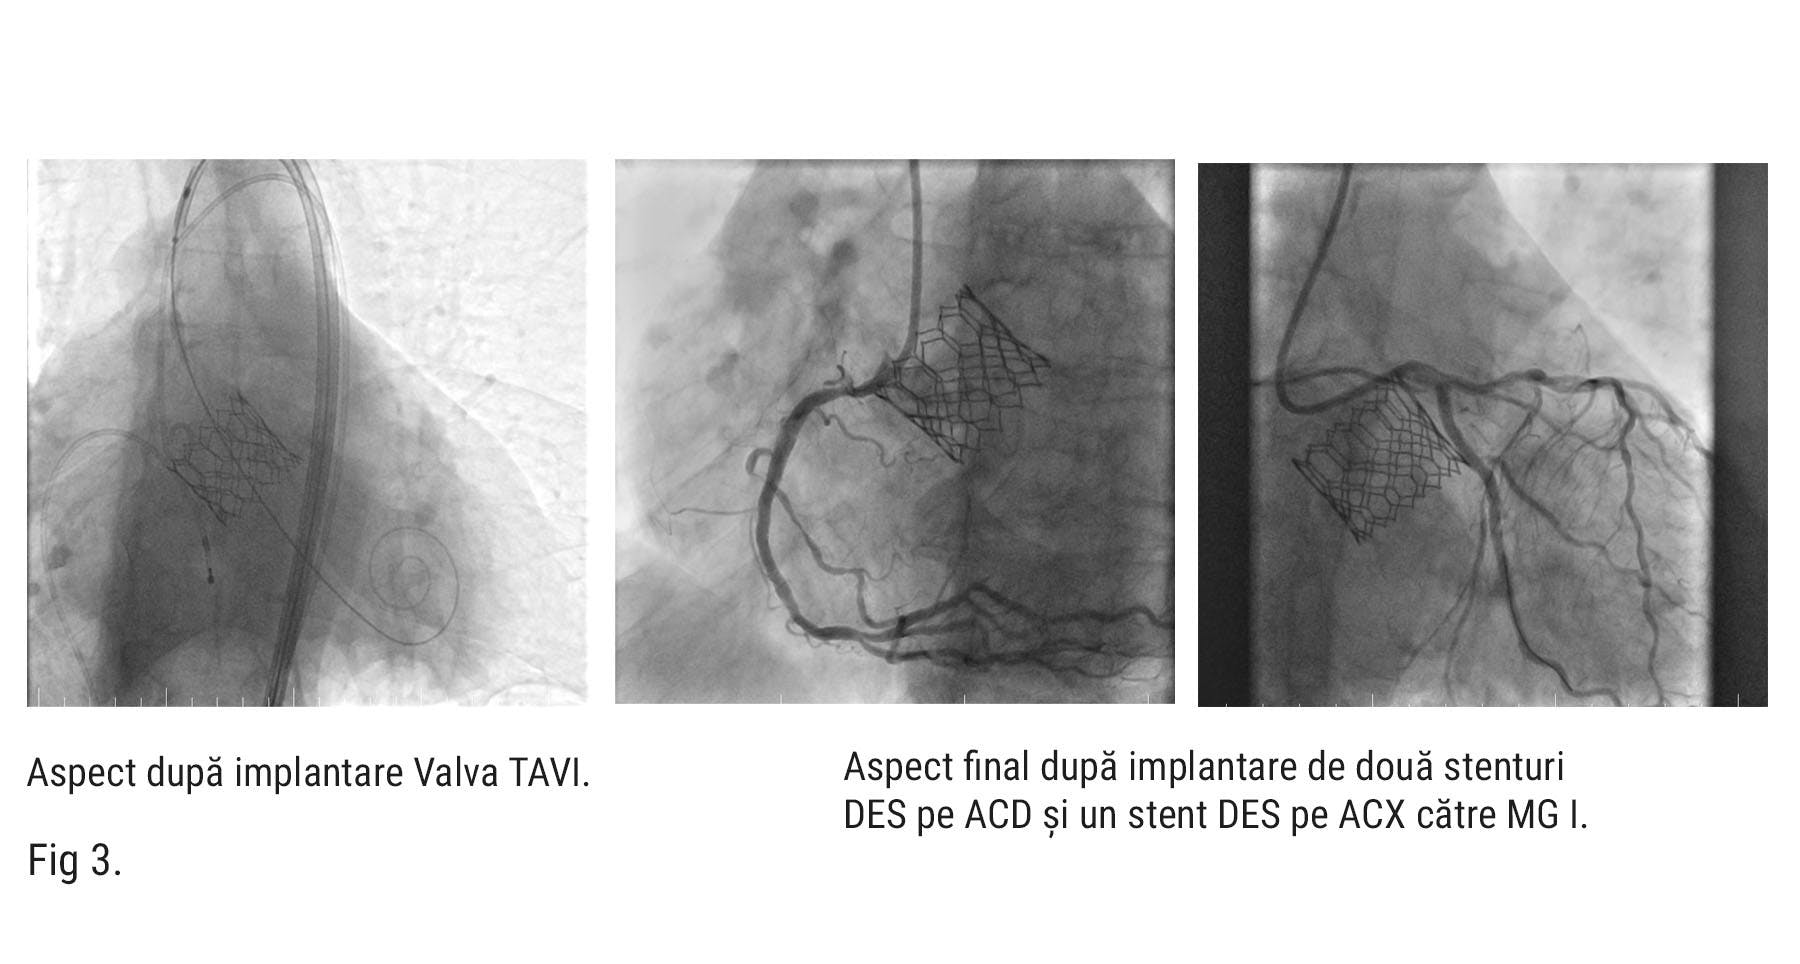

Astfel echipa medicală a efectuat implantarea percutană prin abord transfemural a unei proteze biologice aortice Edwards Sapien 3 de 29 mm, sub sedare profundă și cu ghidaj ecocardiografic transtoracic.

Pe parcursul procedurii, dr. Nicolae Cârstea, a efectuat și o coronarografie care a evidențiat stenoze coronariene semnificative (70-80% în ramurile marginală și ACD (Fig. 1).

Având în vedere boala cronică de rinichi, s-a decis amânarea angioplastiei coronariene o lună după procedura de TAVI. După această perioadă, pacientul s-a prezentat la MONZA ARES Constanța – HEKA Hospital unde dr. Nicolae Cârstea, a efectuat angioplastie coronariană cu două stenturi farmacologice active pe ACD si un stent DES pe ACX către MG I. (Fig. 3 – rezultat final cu stenturi)